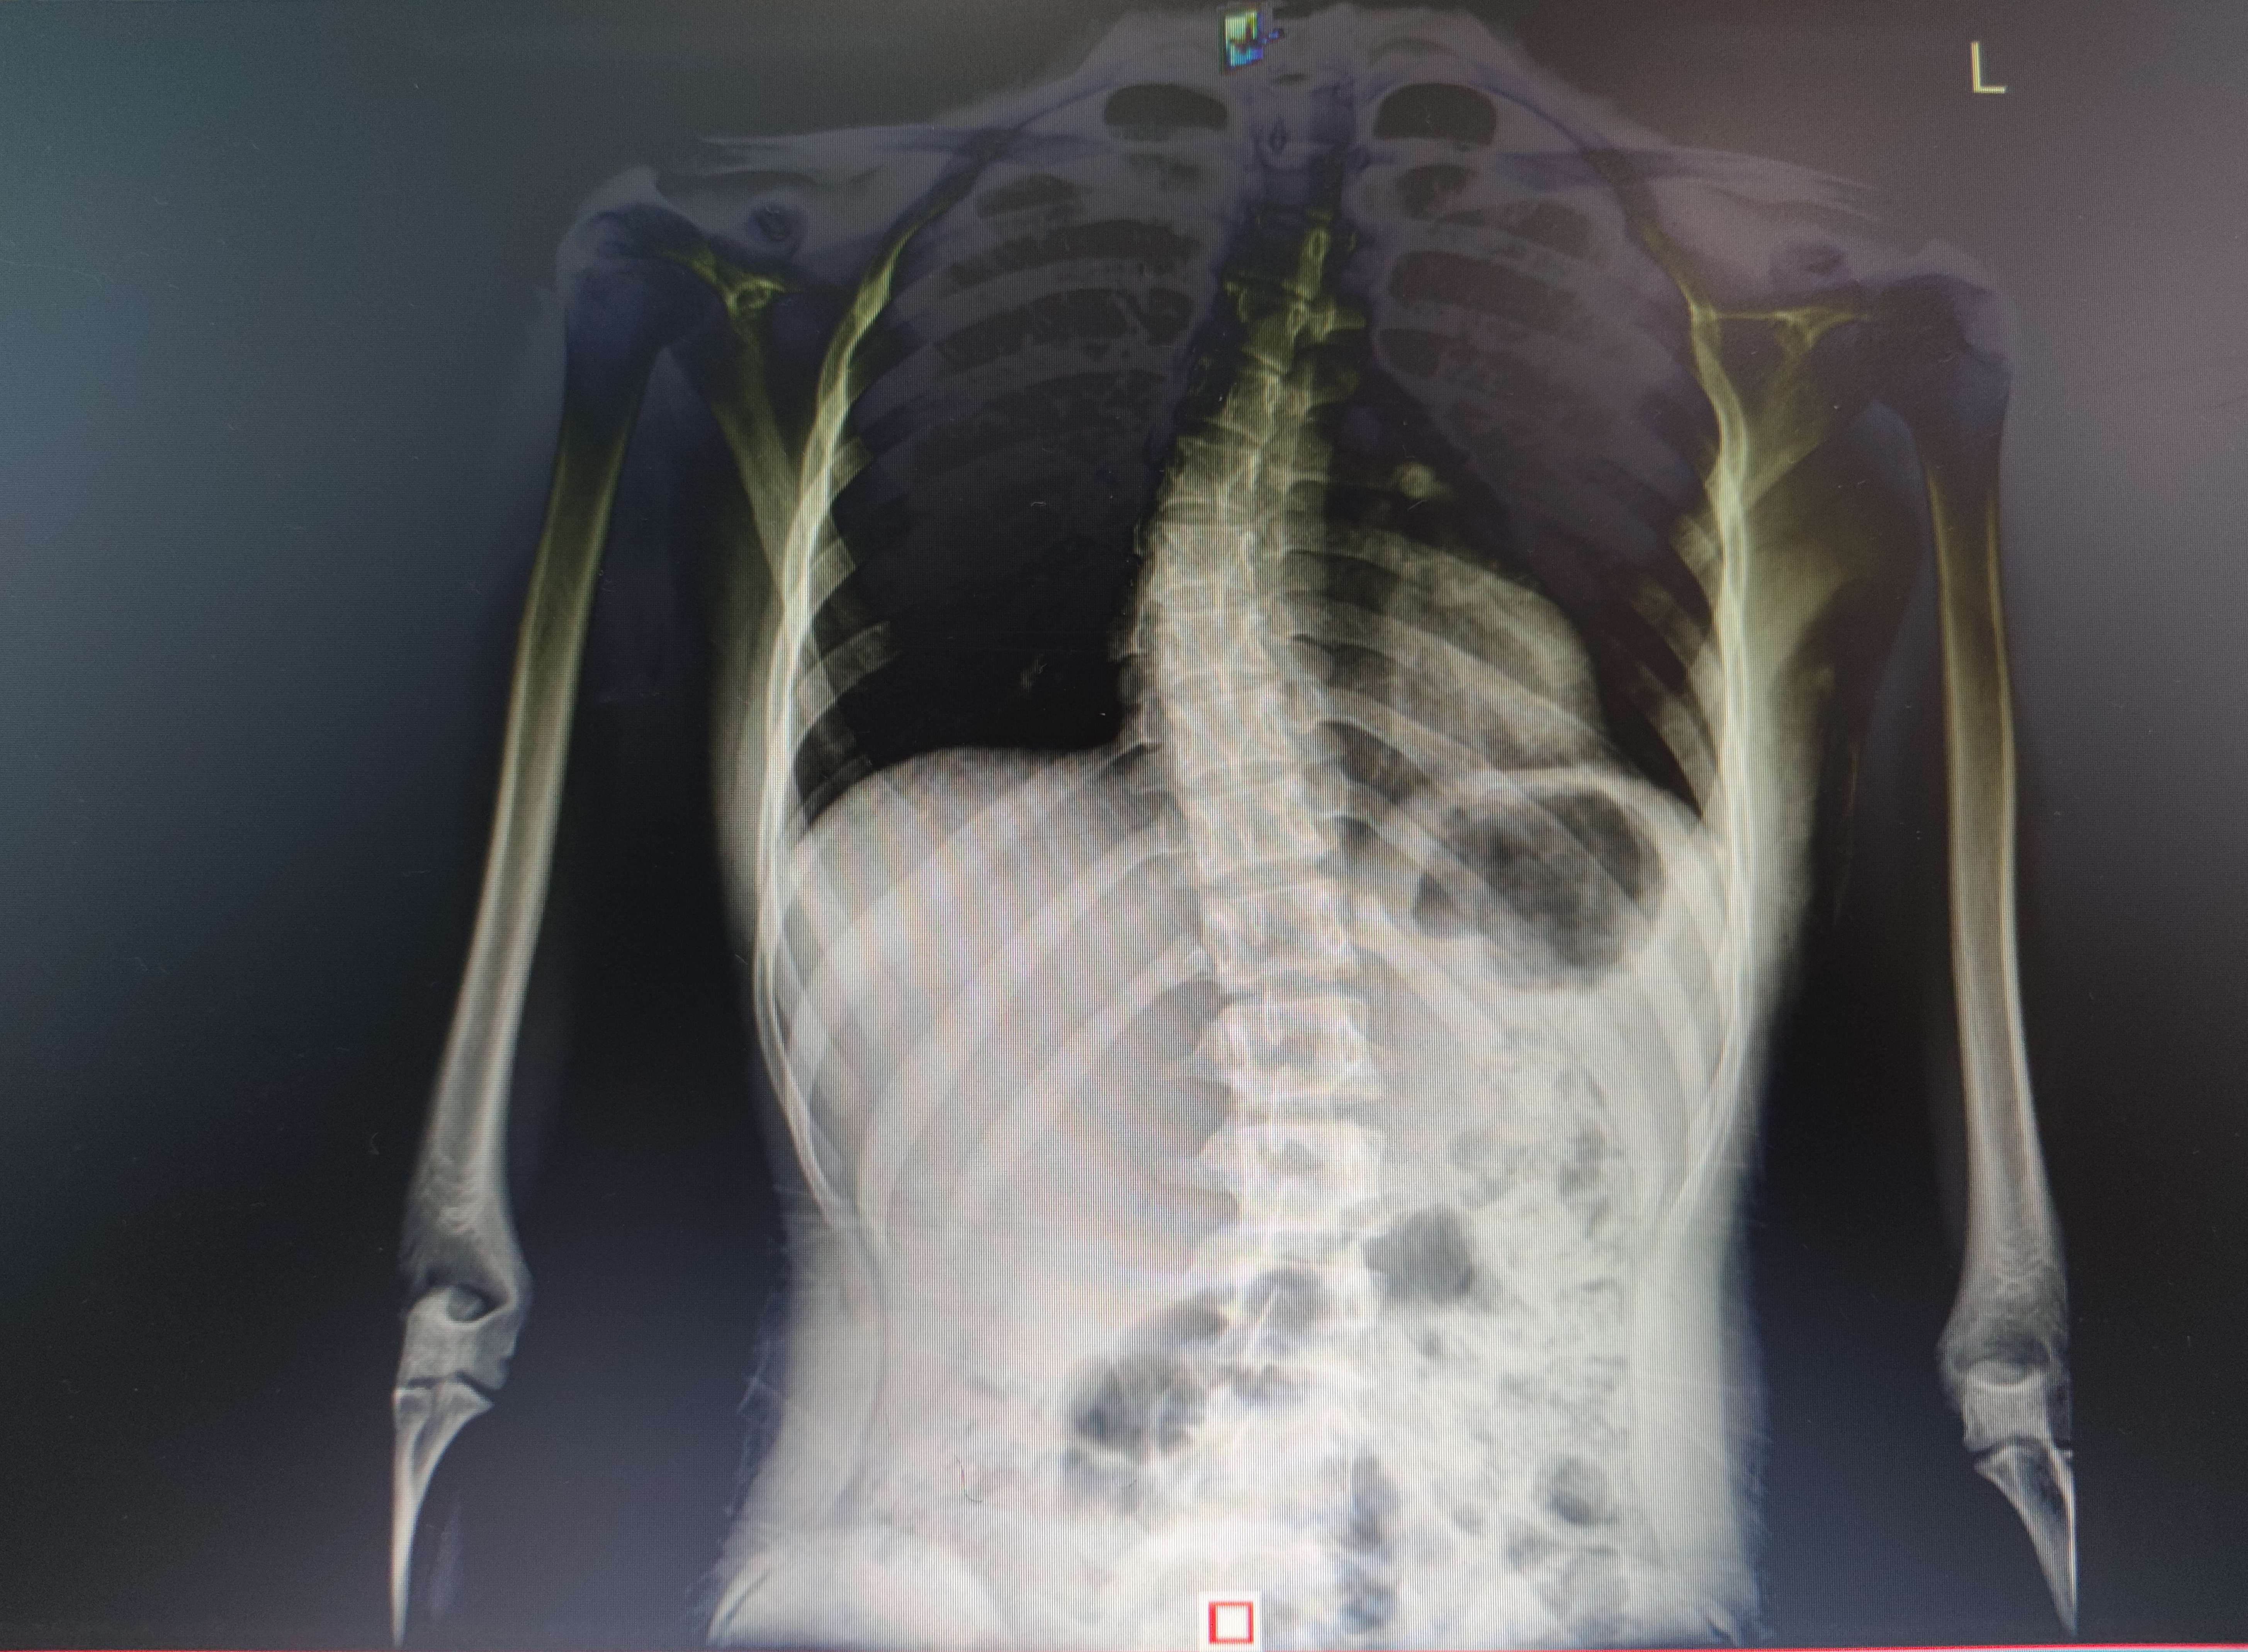

有个小孩,说是在外面到处看了好久,其他医生说不用拍片就都没拍,今天来拍一次果不其然S弯了( ´ー`)

不是说人家庸医,但是庸医真的误人( ´_ゝ`)

>>No.65197279

原来是练舞蹈练出来的( ´_ゝ`)

小孩都不说话,家长说什么练的时候没看出来,不练了之后发现的,现在得上脊柱科搞支具了

不是,姐,说什么怕长不高什么,妳有没有发现就是因为让练舞弄的呢( ´_ゝ`)

>>No.65197304

问什么有没有希望

妳觉得妳的小孩希望练舞连成可能需要做手术吗( ´_ゝ`)

无标题 无名氏 2025-02-05(三)17:48:15 ID:oq5L8xo [举报] No.65200056 管理

小孩的片子

>>No.65200056

结果

小孩真可怜,被家长这样弄